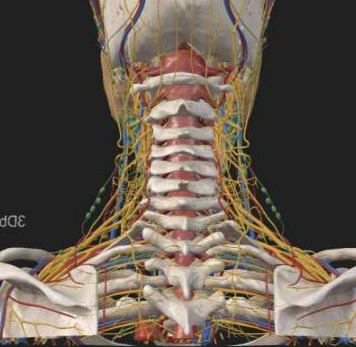

看似确定了治疗方向,真正的难题才刚刚开始。该手术区域解剖结构极其复杂,毗邻人体重要的神经、血管,堪称脊柱外科的“珠峰”。